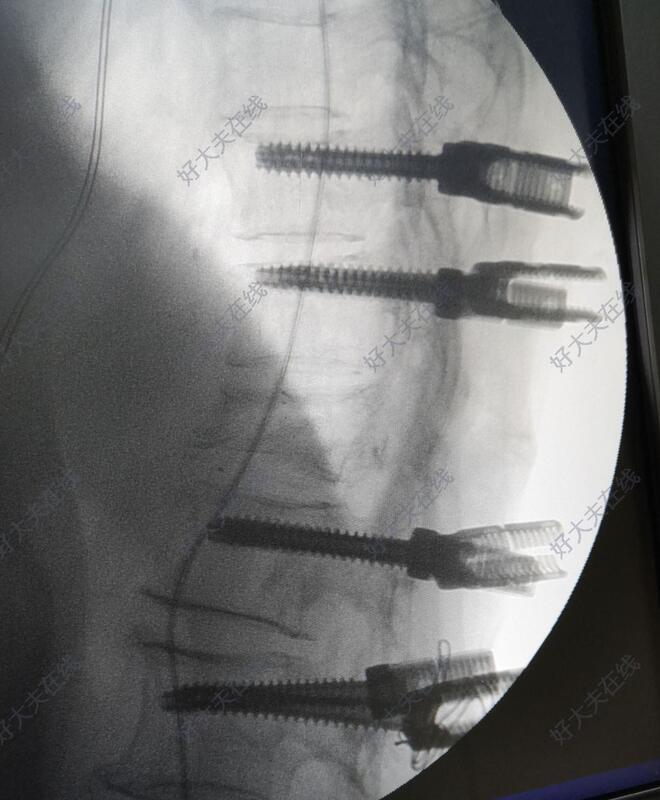

术中于胸10,胸11,腰1,腰2椎体置入骨水泥椎弓根螺钉。透视见骨折复位后,于胸12双侧椎弓根对胸12椎体植骨。

术后3月左右患者来门诊随访。腰背部疼痛完全消失,双下肢活动良好,自行步入病室,步态稳定,患者自觉恢复良好。复查X线提示内固定位置良好,胸腰椎后凸畸形恢复良好。